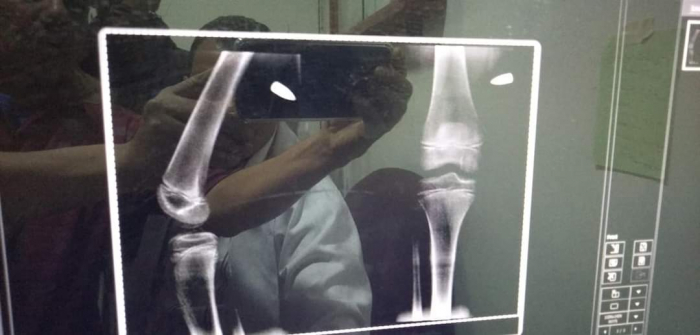

واخترقت الرصاصة، بحسب المصادر، فخذ الطفل، مشيرة إلى إسعافه إلى مستشفى لإخراج الرصاصة، وإيقاف النزيف.